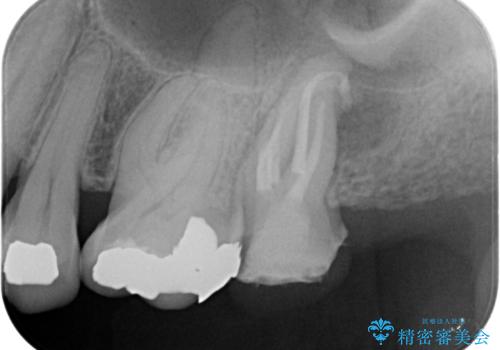

痛みはないとの事でしたがレントゲンを撮影したところ根の先に病巣がある事がわかりました。

被せ物、古い材料を徹底的に除去し、ラバーダム防湿にて無菌的処置を行い、セラミックの被せ物で治療を行いました。

治療が終了してからも定期的にレントゲンをとり経過観察を行いました。

病巣は現在縮小しておりまた白い被せ物が入り患者様に満足してもらえました。